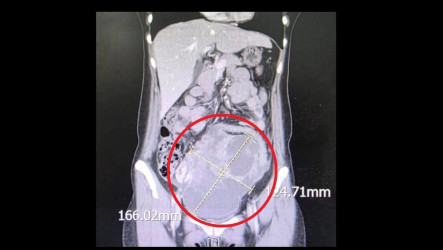

透析室護理團隊發現畢小姐體重異常增加,腹部隆起看似腹水,更從腹部感受到微弱規律震動,透析室建議畢小姐前往婦產科檢查,結果已懷孕21週,胎兒發育正常,「我當天晚上還跑到婦產科診所再確認一次」,畢小姐說,看著超音波螢幕裡的小生命,丈夫直說要破產了。

進入懷孕後期,挑戰更加艱鉅。「我們像走在高空鋼索的人」,長庚醫院婦產科主治醫師黃詩穎說,畢小姐出現重度子癲前症徵兆,血壓攀升,甚至併發肺炎、肺水腫及心瓣膜脫垂等心肺危機,啟動跨專科會診才穩定病情。為了確保母嬰安全,懷孕31週時,團隊果斷決定進行緊急剖腹生產。